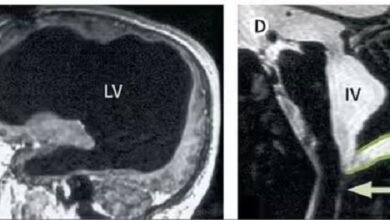

लड़की को थी दिल की अजीब बीमारी, हाथ-पैरों की नब्ज गायब, रिपोर्ट देख डॉक्टर भी चौंके

कानपुर के रेजेंसी हॉस्पिटल में डॉक्टर शशांक त्रिपाठी और उनकी टीम ने नेपाल की 22 वर्षीय युवती की एक बेहद…